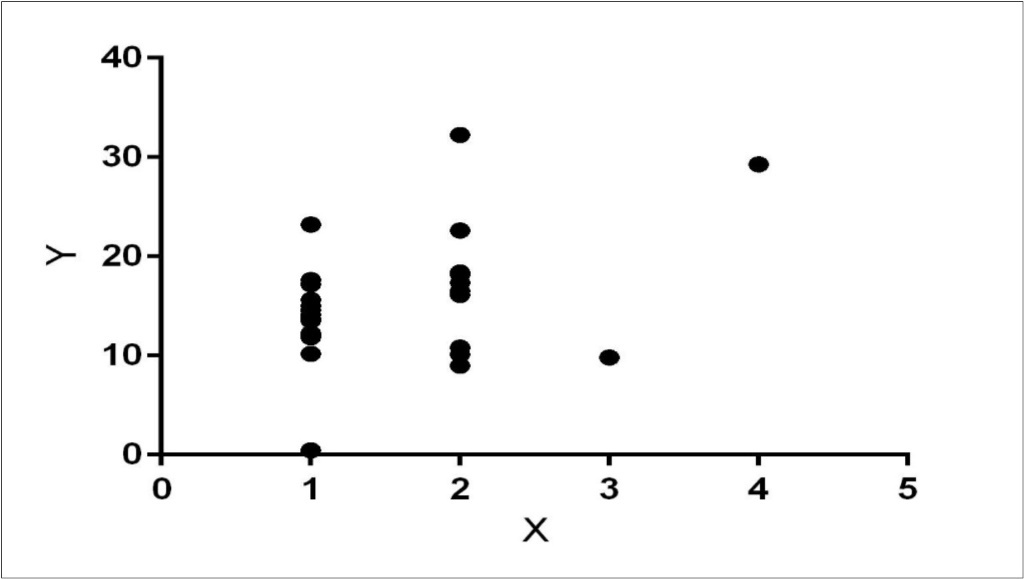

There was a significantly positive correlation (Figure 2) between serum cortisol level and MTLA scores (Pearson Correlation Coefficient=0.39, p<0.05). Similarly, a significantly positive correlation was present between serum cortisol and CSDD Scores (Pearson Correlation Coefficient=0.49, p<0.05).

Figure 2.Linear regression showing correlation between serum cortisol (y) and MTA scores (x).

There was a significantly negative correlation between MMSE and MTA scores (Pearson Correlation Coefficient=0.60, p<0.0001). No significant correlation between age and MTA scores was observed. A positive correlation between CSDD and MMSE was also present (r=0.40, p<0.05). One way Analysis of Variances (ANOVA) test was performed using standard weighted-means analysis to see if the groups with MMSE scores, MTA scores, serum cortisol and CSDD scores were significantly different from each other. ANOVA showed a highly significant difference between groups (p<0.0001). Tukey’s Honestly Significant Difference Test showed that all 4 independent groups at alpha level of significance (0.05) were significantly different from each other. Odds ratio of serum cortisol in AD/MCI was 3.4 (95% confidence interval=0.3197 to 37.4751), however the p-value was not significant.